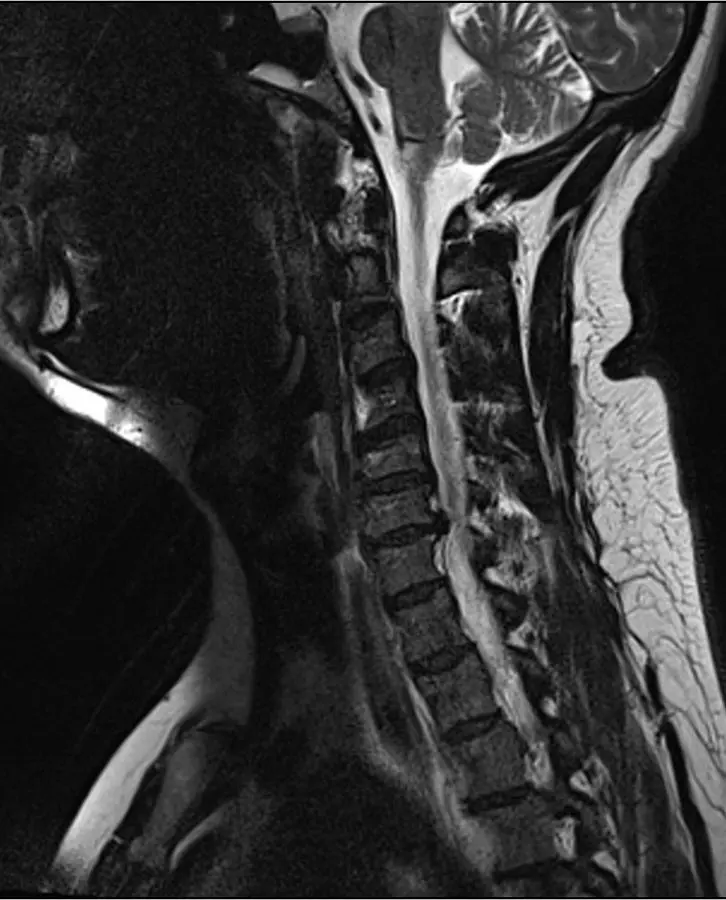

18. Imaging of the Head and Neck